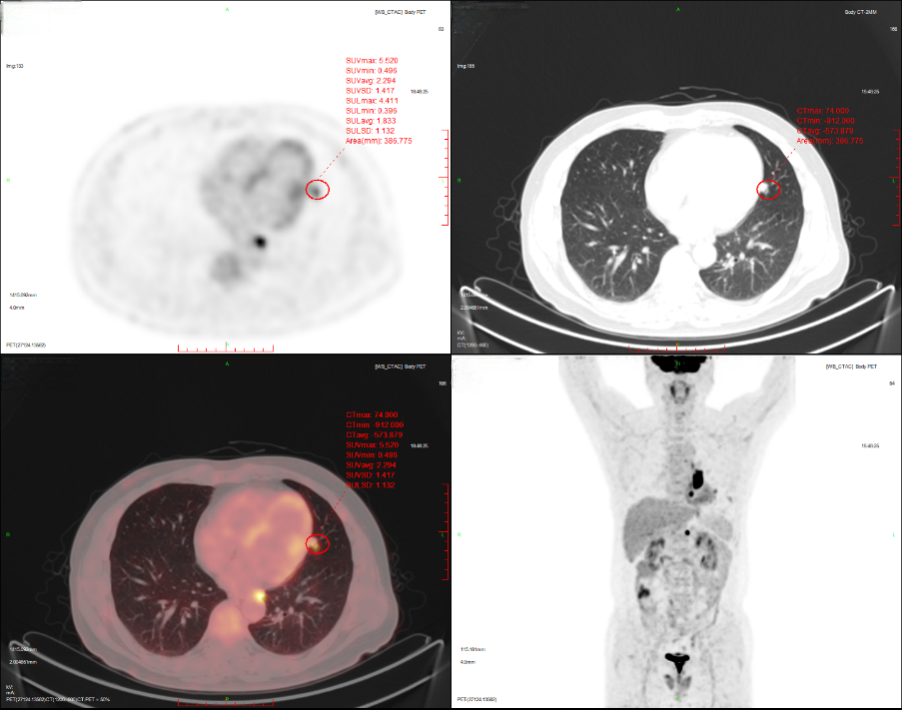

2024-11-26 PET-CT进一步评估:左肺下叶背段近肺门处类圆形分叶状肿块(约32*28mm),FDG代谢异常增高;纵隔内4L组、左下肺门处、左侧膈肌脚内侧见稍大淋巴结FDG代谢增高,左肺内及胸膜下散在多发结节影,FDG代谢不同程度增高,考虑左肺下叶肺癌伴左肺及胸膜多发转移、多发淋巴结转移。

基因检测:检出I类变异LINC00707(Intergenic)-ALK(Exon20-29)。

左肺恶性肿瘤(左肺腺癌IVA期,cT2aN2M1a,胸膜),LINC00707-ALK融合,TPS 0%,PS评分1分。

2024年12月11日,予洛拉替尼100mg QD治疗。